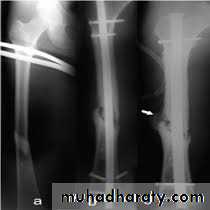

X-ray :

Shows the type of fractures, and displacement. The x-ray should include the hip and knee and x-ray of pelvis to avoid missing segmental fractures, knee injuries, fractures of neck of femur, dislocation of hip, fractures of acetabulum and pelvis.

Fixation of femoral shaft fracture